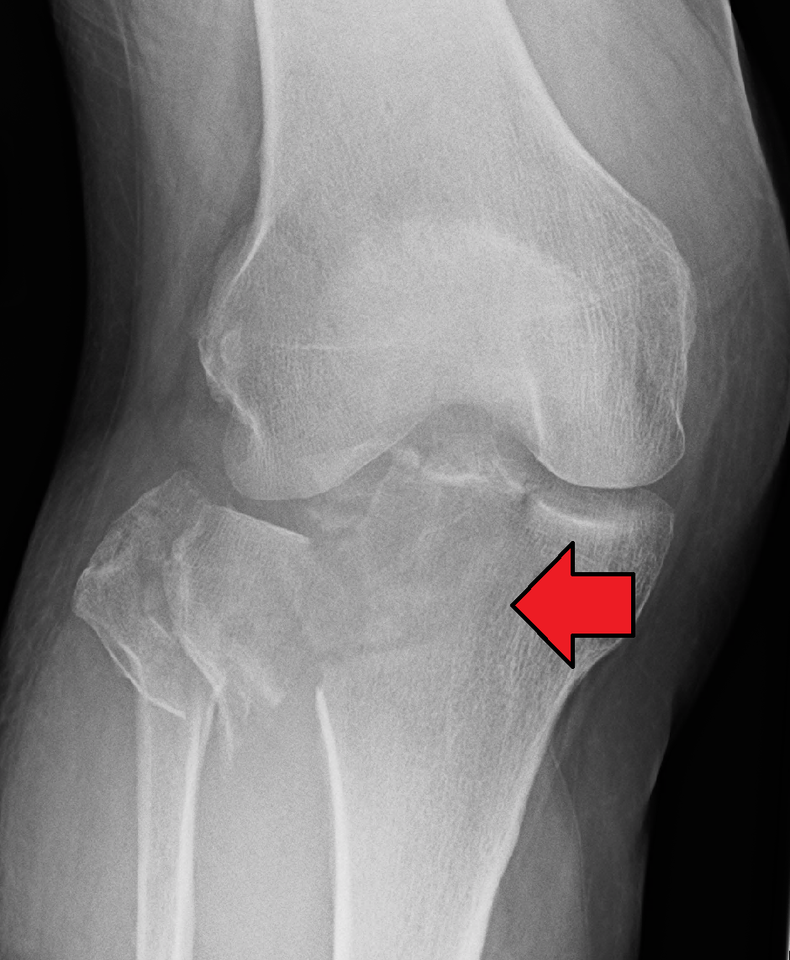

Основные симптомы перелома колена

Такое опасное повреждение может внутрисуставным и внесуставным. В свою очередь, внутрисуставные повреждения делятся на открытые и закрытые. Они могут сопровождаться и другими повреждениями в виде разрыва связок, менисков, образования сосудисто-нервных пучков. Обнаружить перелом колена можно по следующей тревожной симптоматике:

- Деформация суставного элемента.

- Деформация колена.

- Вторичное смещение костей и мыщелковых осколков.